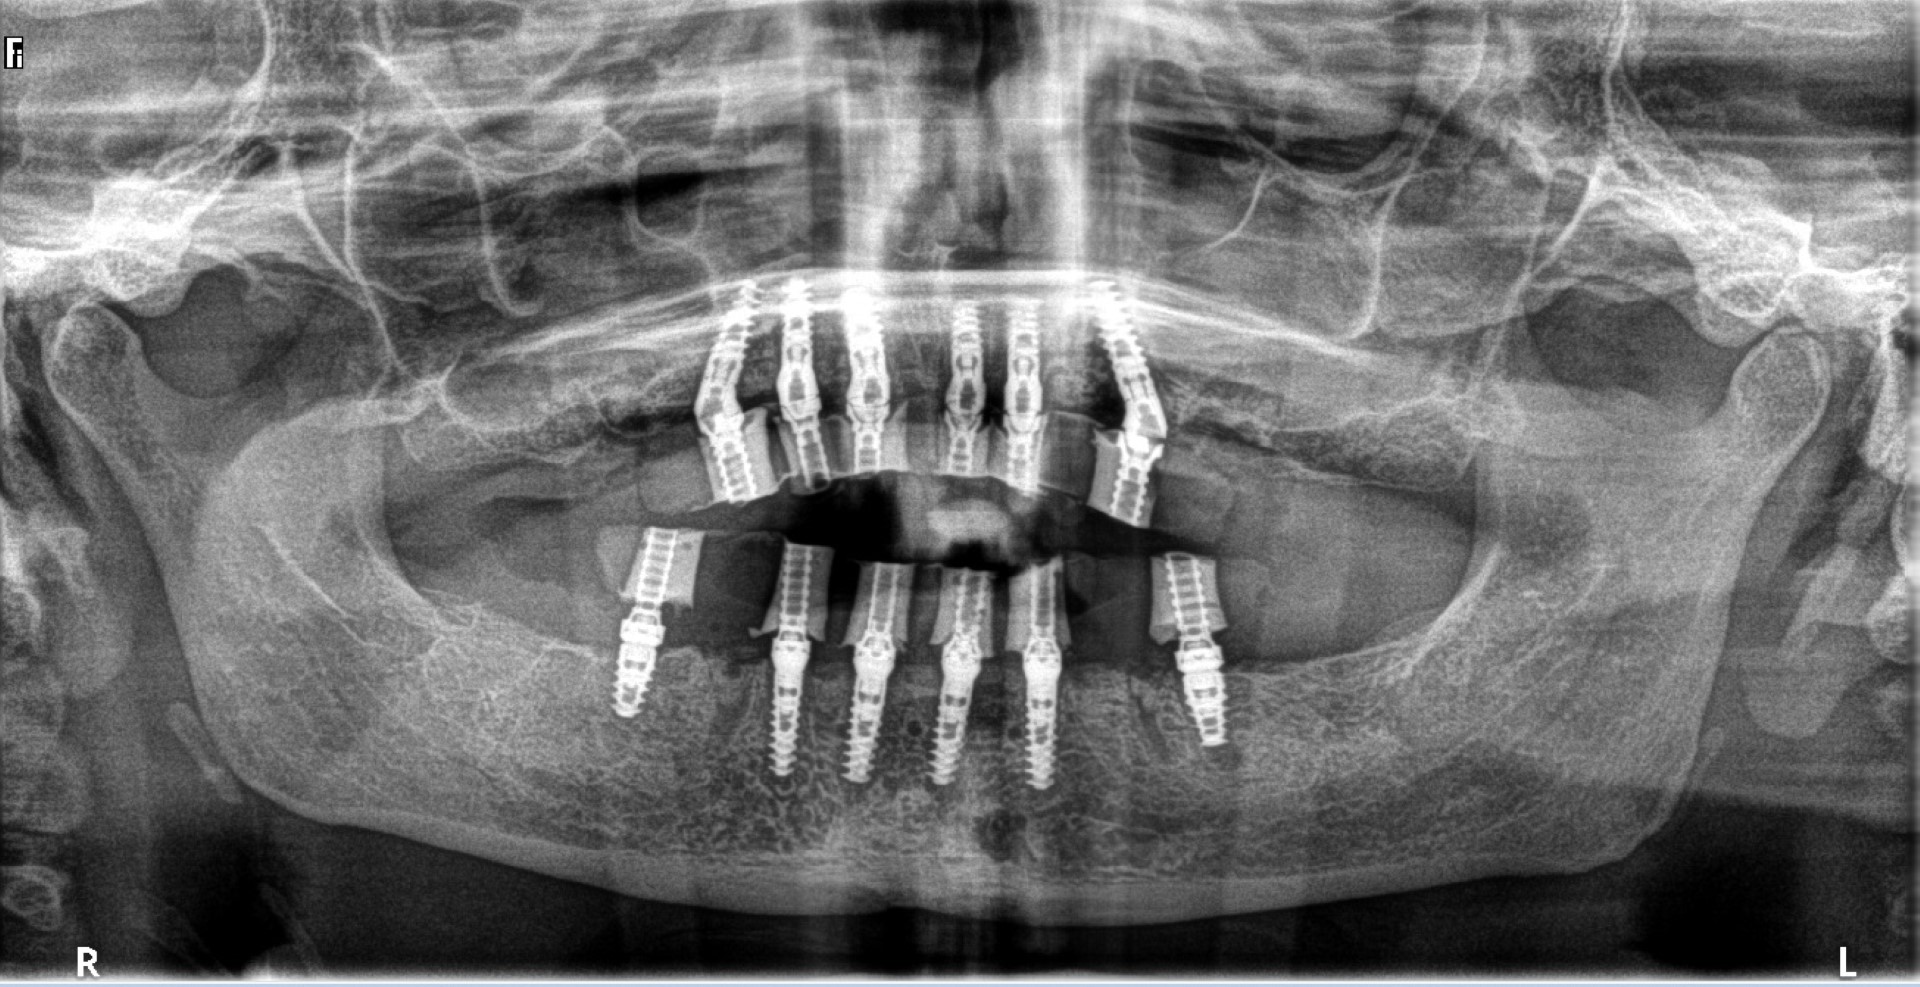

Why CBCT (Cone Beam CT Scan) is a Must for Patients Receiving Dental

Why CBCT (Cone Beam CT Scan) is a Must for Patients Receiving Dental Dental Implant Artifact The aims of this study were to develop a computed tomography/magnetic resonance (ct/mr) oral. Cbct artifacts were investigated in images integrated at 0.25 mm, 10 mm, and 20 mm at regions of interest on concentric circles at. Effectiveness of dect and mar algorithms. Titanium implants cause the greatest relative errors in se techniques. Metal artifact are common and decrease diagnostic. Dental Implant Artifact.